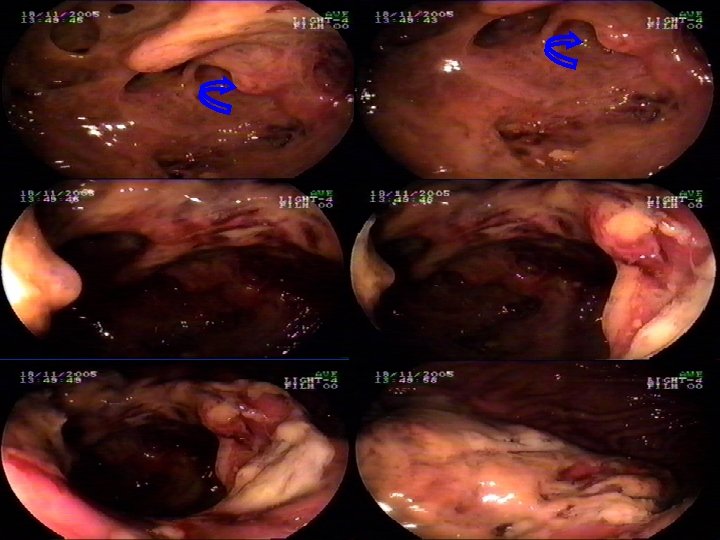

PUNCION GASTROQUISTICA DE URGENCIA EN PSEUDOQUISTE A TENSION FUERA DE ALTERNATIVA QUIRURGICA ABIERTA Y DE PUNCION POR RM O TAC INFORME MEDICO Paciente de 40 años de edad, con el antecedente de 7 años de crisis de Pancreatitis Aguda recurrente, aparentemente por hipertrigliceridemia. Los ultimas crisis ha sido hospitalizado por su médico tratante en UCI del Hospital del Trabajador, su última crisis mantiene durante 40 días UCI con Pseudoquiste Residual. Controles posteriores revelan aumento progresivo en el tamaño del mismo, llegando a dimensiones de 500 cc, en Enero de este año. El paciente vuelve a presentar crisis en Agosto del 2005, siendo hospitalizado nuevamente. (Su Isapre habría manifestado problemas puntuales por lo prolongado de su hospitalización en UCI) Control de esta oportunidad por TAC es calculado en 500 cc imageneológicamente, pero sin control gastroenterológico posterior. Durante el fin de semana llega nuevamente el paciente a hospitalizarse con diagnóstico de Pancreatitis crónica reagudizada, experimentando intenso dolor en faja de 48 hrs de evolución con reaparición de abultamiento supraumbilical, intensamente doloroso a la palpación superficial, corroborandose posteriormente la presencia de un Pseudoquiste evolucionando, de un tamaño de 1. 380 cc (1. 500 cc); por este motivo se solicita evaluación con TAC que demuestra signos de hipertensión portal en las paredes gástricas externas y compresión de la pared gástrica posterior.

Endosonografía más EUS Gástrica con punción pancreática n Paciente presenta, en esta oportunidad, intenso dolor cólico abominal irradiado al dorso. n Dentro de este cuadro clínico es posible apreciar pseudoquiste pancreático con gran aumento en los últimos 4 meses, con una evolución clínica formal de 6 -7 años y múltiples hospitalizaciones en UCI y sala. Ante la eventualidad que exista compresión gástrica se planifica Endosonografía más EUS Gástrica con punción pancreática, una vez decartada la alternativa quirúrgica por el equipo de cirujanos digestivos del Hospital y por el encargado de imageneología terapéutica, previa evaluación de su estado de coagulación. n n De acuerdo a las características de la lesión (volumen mayor a 1. 380 cc, con imágenes heterogéneas en su interior, se evalúa la necesidad de punción con estudio completo de liquido incluido estudio citológico/histopatológico (así llamado cito histológico en agar). (Kawaguchi et al. para manejo de su compromiso sistémico, pues debe descartarse una; Neoplasia Cistomucinosa del Páncreas, Infección de la Cavidad Quística Pancreática, filtración desde la cavidad al Peritoneo).

Dentro de las conclusiones se decide urgente de realizar punción, motivo por el cual se cita a reunión de urgencia con cirujanos digestivos de turno y el el Médico imageneólogo de turno para evaluar por última vez alternativa quirúrgica, la cual es descartada por el gran riesgo quirúrgico y planteando como unica alternativa punción bajo EUS. Debido al riesgo vital que implicaba técnicamente desde el punto de vista de Cirugía abierta, drenar una cavidad de estas características y lo mismo para un drenaje por TAC, aceptamos como UNIDAD DE GASTROENTEROLOGIA DEL HOSPITAL DEL TRABAJADOR DE CONCEPCION ESTA DECISIÓN PREVIA CONSULTA CONSENTIMIENTO INFORMADO AL PACIENTE Y A SU ESPOSA DENTRO DE NORMA DEL HOSPITAL , LA CUAL SE RIGEN POR ISO 9001. Posterior a reunión clínica se decide examen, según detallo: PROTOCOLO MANEJO ENDOSCÓPICO DE ESTAS LESIONES PANCREÁTICAS: I. - Endoscopia Digestiva Alta, para localización macroscópica del área adecuada. Determinar si esta presente la compresión extrínseca gástrica. II. - Endosonografía Pancreática, Se realiza para que en caso de existir confirmación de la existencia de compresión extrínseca; puncionar con marca biópsica del área menos vascularizada de la pared gástrica (Antecedente por TAC de Hipertensión Portal). III. - Perforación Gastro quística, Una vez localizado el punto mas adecuado, se marca con precut de corte/coagulación 3. 0/3. 5; y luego de penetrada la pared, se realiza penetración con aguja de punción de balón, aspirando contenido quístico y corroborando lo anterior por apoyo de rayos X.

Finalmente, mediante enfinterótomo de nariz larga se realiza canulación corte en un área de 1. 5 cm a 2 cm. Se espera la salida del líquido y porterior a ello, se intenta la introducción de una guía para drenarla instalada en la cavidad mencionada. Para esta maniobra se requiere el uso de rayos. En caso de existir material sólido de grandes proporciones se abre una cavidad mayor con esfinterótomo entre dos puntos abiertos previamente (a una distancia de 2 -3 cms de distancia uno de otro) IV. - Tubo de drenaje, de acuerdo a las características del líquido drenado (sanguinoliento o purulento). - V. - Finalmente se toman muestras para: Cultivo anaerobios y habitual - Citologia (Patología) - Estudio bioquímico del líquido - Estudio de amilasa – Lipasa – Proteínas. VI. - Localización del paciente, de acuerdo a evolución posterior al procedimiento: - Sin compromiso hemodinámico, se deja con reposo y control cada 2 horas en 1 eras. 6 HORAS y luego transfusión PARA COMPENSAR ELcompromiso hemodinámico.